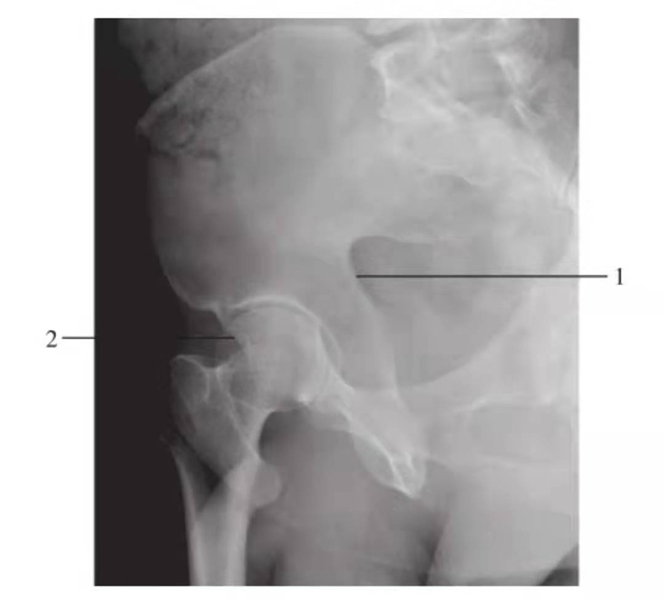

闭孔斜位

图9 右侧闭孔斜位

1.前柱;2.髋臼后唇

髂骨斜位

图10 右侧髂骨斜位

1.后柱;2.髋臼前唇